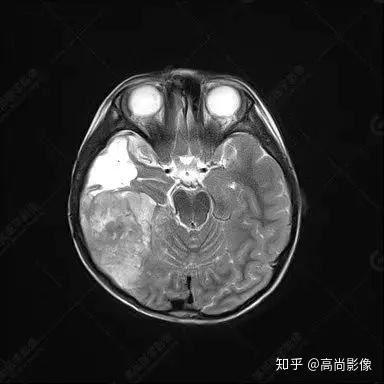

右側(cè)顳葉腫瘤切除術(shù)后(具體不詳):右側(cè)顳部骨質(zhì)不連續(xù)呈術(shù)后改變,右側(cè)顳葉術(shù)區(qū)見片狀長T1長T2信號(hào)影,F(xiàn)LAIR呈低信號(hào);術(shù)區(qū)后方右側(cè)顳枕葉見一巨大占位性病變影,邊界欠清,大小約6.2×5.8×4.3cm(前后×左右×上下),信號(hào)不均勻,T1WI呈等稍低信號(hào)間雜少許高信號(hào),T2WI呈高稍低混雜信號(hào),DWI示部分病灶彌散受限,相應(yīng)ADC圖減低,磁敏感序列見部分呈極低信號(hào),增強(qiáng)掃描可見明顯不均勻強(qiáng)化,鄰近硬腦膜及小腦幕增厚并明顯強(qiáng)化;另延髓右前方及右側(cè)橋小腦角區(qū)見一不規(guī)則形異常信號(hào)影,大小約3.2×1.3×3.7cm(左右×前后×上下),呈長T1稍長T2信號(hào),F(xiàn)LAIR呈等信號(hào),DWI未見受限,增強(qiáng)后明顯均勻強(qiáng)化,鄰近腦膜明顯強(qiáng)化。鄰近腦實(shí)質(zhì)及右側(cè)顳角明顯受壓;左側(cè)大腦半球未見局灶性信號(hào)異常,中線結(jié)構(gòu)稍左移。

右側(cè)顳葉腫瘤切除術(shù)后:現(xiàn)術(shù)區(qū)后方右側(cè)顳枕葉及延髓右前方占位,右側(cè)顳枕部硬腦膜及小腦幕明顯強(qiáng)化,結(jié)合既往影像資料,考慮為胚胎源性惡性腫瘤,如非典型畸胎樣/橫紋肌樣瘤(AT/RT)或原始神經(jīng)外胚層腫瘤(PNET)。